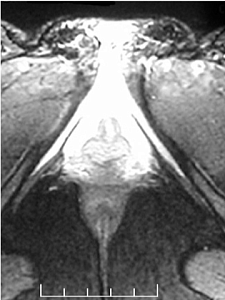

The first MRI of the clitoris

Odile Buisson

Helen O'Connel